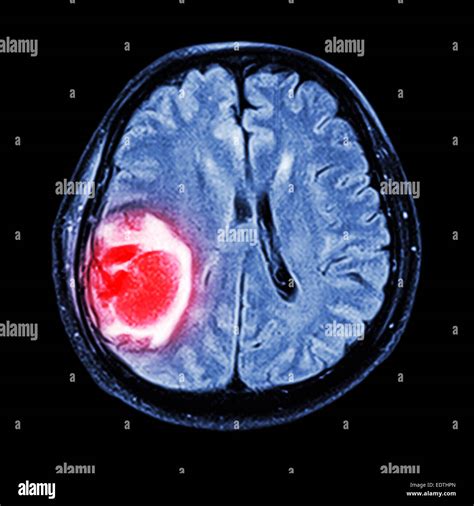

Brain Tumor Symptoms and Types - Health and Disease

tumor brain types symptoms causes